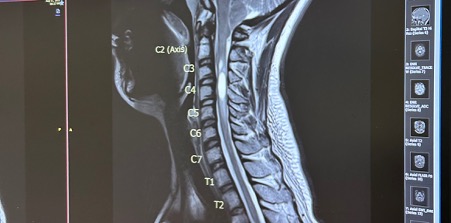

Chiari Malformation With Syringomyelia: Understanding The Condition September is Chiari Malformation Awareness Month – a time to highlight a rare but serious neurological condition that affects the brain and spinal cord. My Chiari Story It was December 2022, and I was sitting in a booth